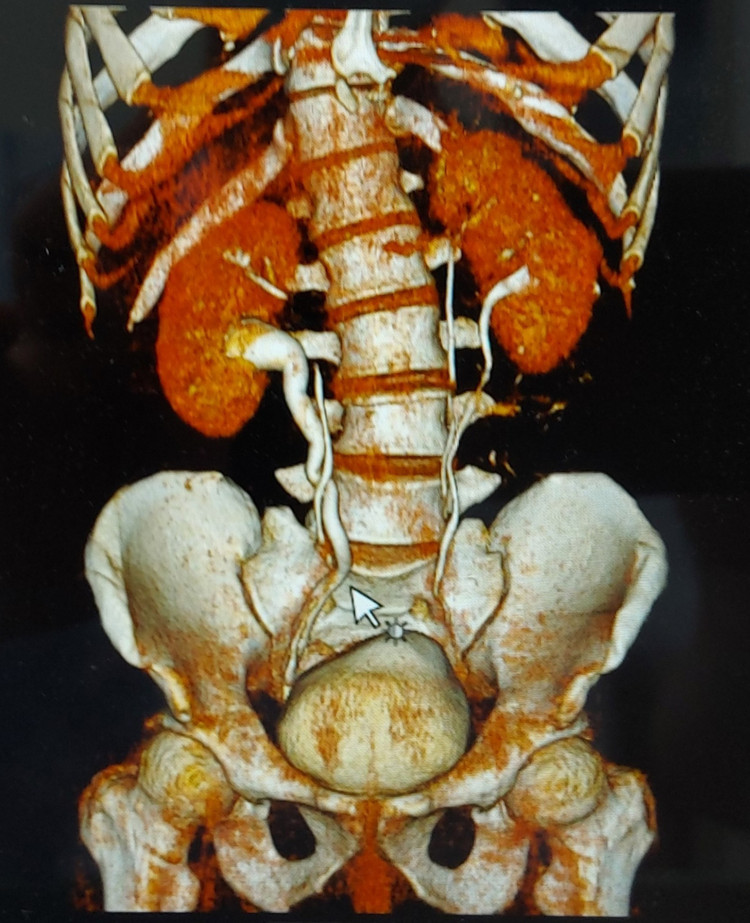

|

| Hình ảnh thận của bệnh nhân trên phim chụp - Ảnh: BVCC |

Bất ngờ hơn, kết quả chụp CT các bác sĩ phát hiện người bệnh có thận niệu quản đôi hoàn toàn hai bên trái, phải và hai niệu quản riêng biệt đều cắm xuống bàng quang. Người bệnh có bất thường về giải phẫu hệ tiết niệu, có nhiều đơn vị thận hơn bình thường là một trong những nguyên nhân hình thành sỏi thận.